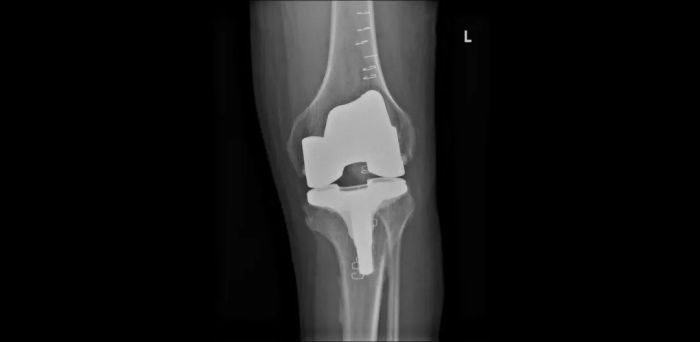

患者术后CT检查结果